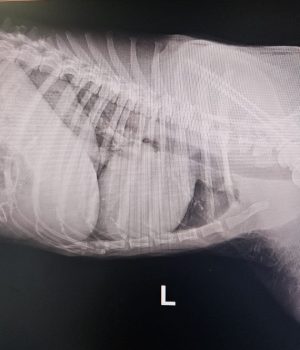

Seine Verletzungen waren schwer: mehrere Brüche der hinteren Gliedmaßen, schlechte Blutwerte und massive Verletzungen im Gesichtsbereich.

Inzwischen hat er zwei schwere Operationen an den hinteren Beinen sowie eine aufwendige Gesichtsrekonstruktion erstaunlich gut überstanden.